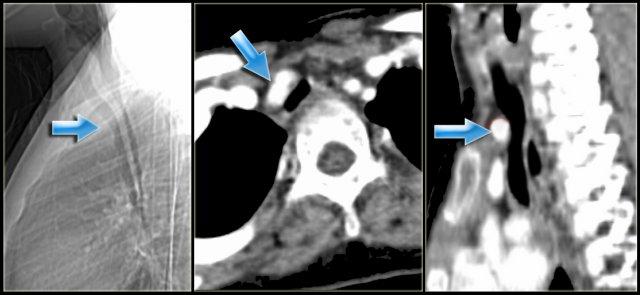

Double Arch with Atretic Segment

Occasionally the double arch can have an atretic segment.

You should not confuse it for a right arch.

The left arch is just very small and there is still a four vessel sign.

On the left a dominant right arch and a small left arch.

The atretic segment is marked by the arrow.

Notice the four vessel sign.

On a posterior view the interruption is nicely demonstrated.

Remember that there is still a ring, so there is still obstruction.

Another case on the left.

Do not call this a right arch.

It still is a double arch and there is a atretic fibrotic segment on the posterior side of the left arch, that completes the ring.

Same patient.

Always look at the airways.

On the recoonstruction the impression on the trachea is better appreciated.